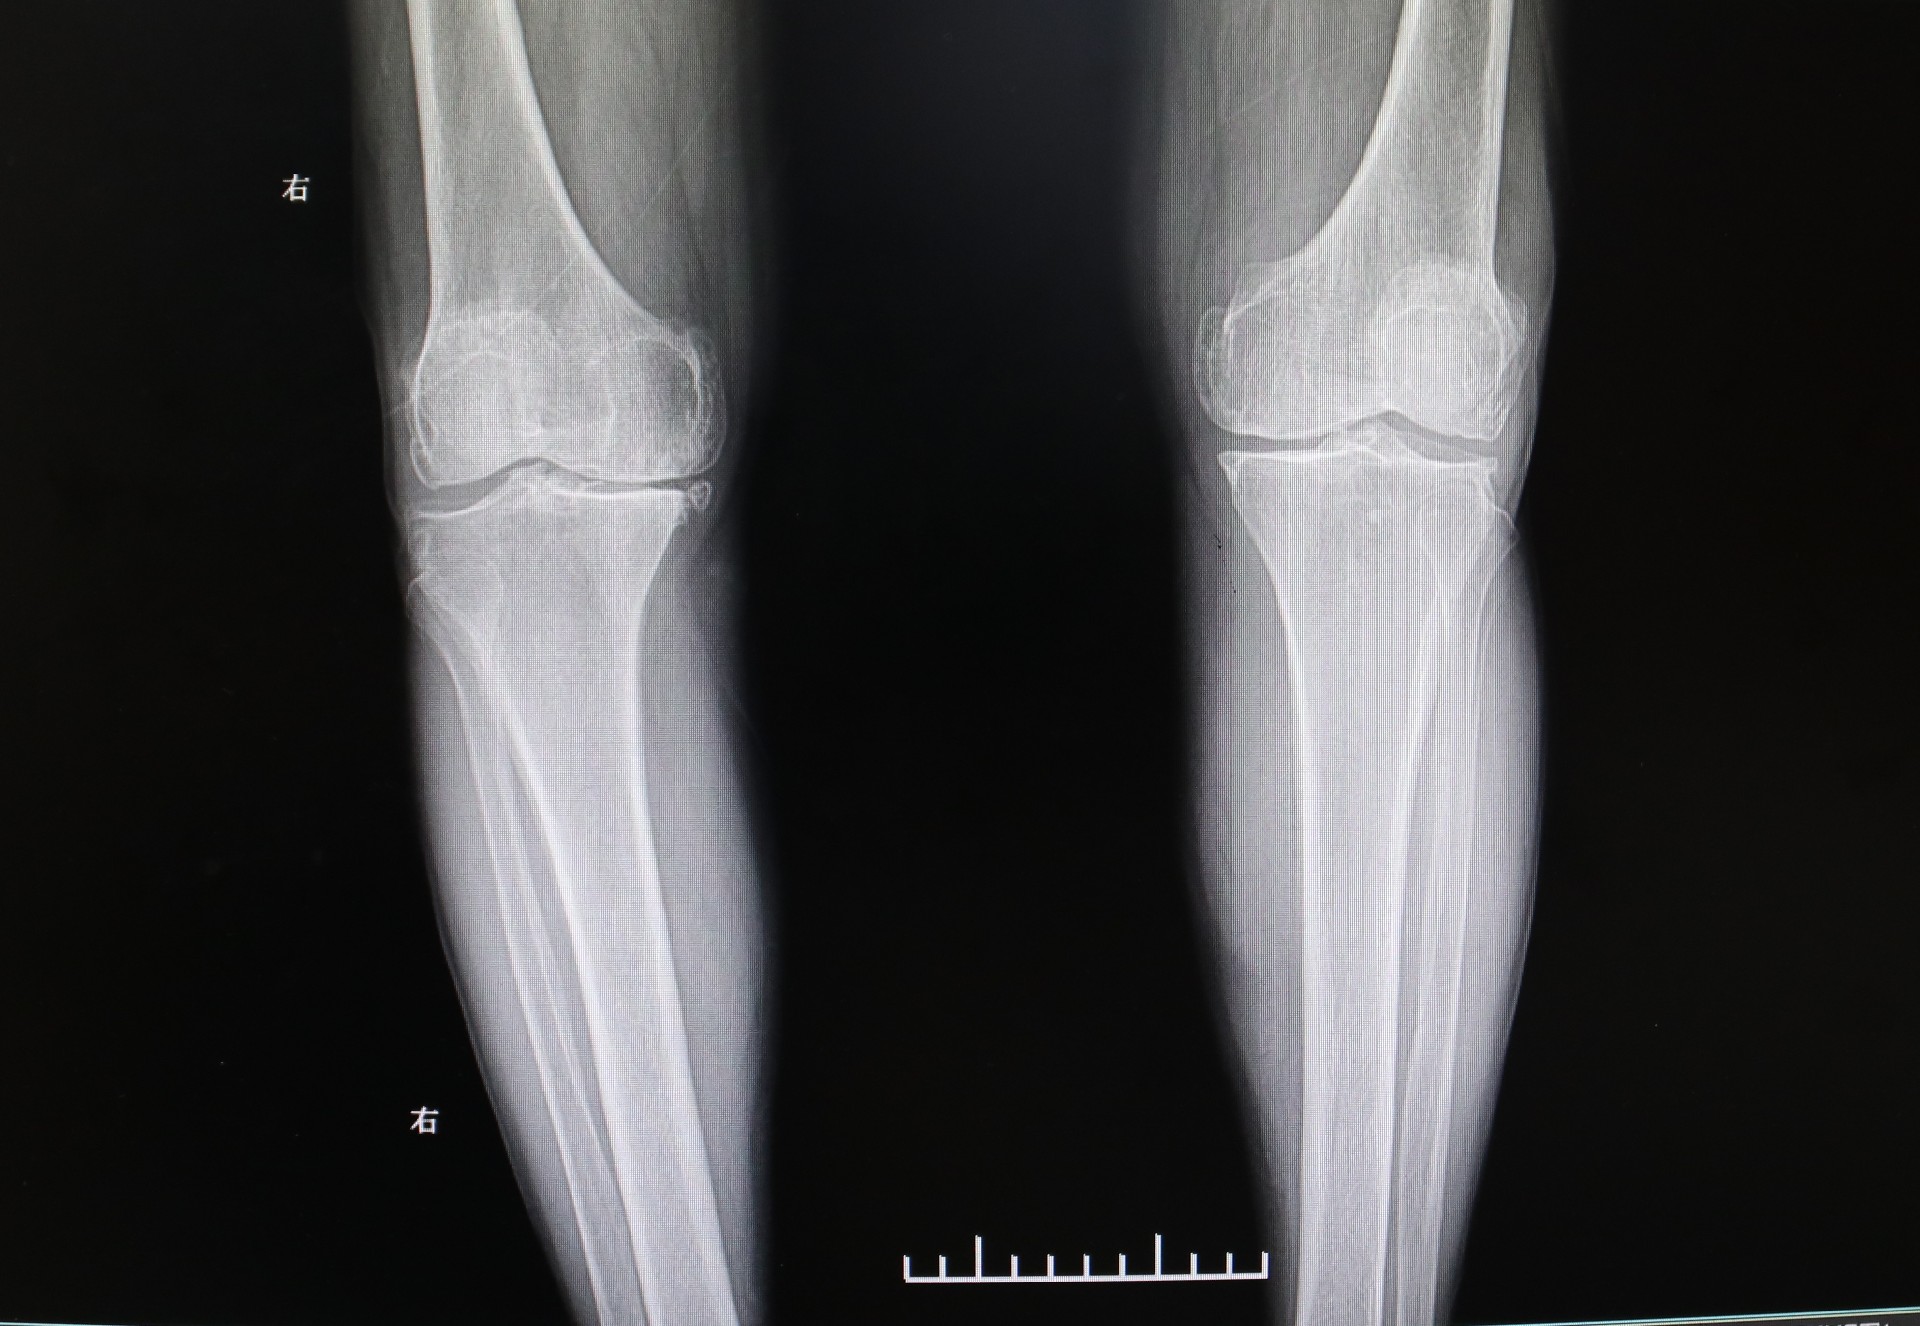

膝关节表面覆盖着软骨,随着年龄的增加,软骨会逐渐磨损,膝关节周围的骨骼、韧带也会发生退变。这使得老人膝盖处骨头间的摩擦加剧,痛苦万分,出现了膝关节疼痛、畸形以及活动障碍等情况。刘海亮主任仔细为老人检查,发现他已是终末期骨性关节炎,保守治疗已经起不到任何效果,针对这类情况,通常考虑进行膝关节置换手术,可有效解决膝关节磨损、矫正变形,并消除患者的疼痛。